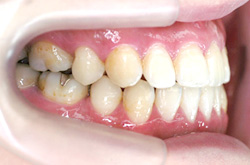

側 面

before

after